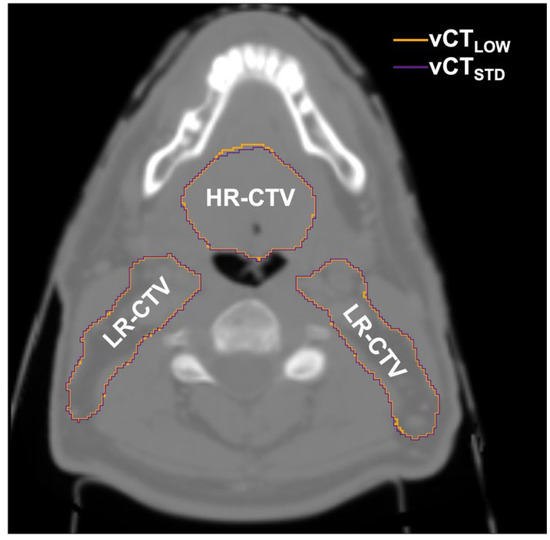

| ROI | DVH Metric | CTDIvol (mGy) | ||||||

|---|---|---|---|---|---|---|---|---|

| 166.0 | 83.0 | 41.5 | 20.7 | 10.4 | 6.2 | 4.2 | ||

| High-risk CTV | D98 (%) | 97.1 (94.5–98.5) | 97.1 (94.8–98.6) | 97.1 (94.6–98.5) | 97.1 (94.6–98.5) | 97.2 (94.9–98.5) | 97.2 (95.0–98.5) | 97.2 (94.7–98.5) |

| Low-risk CTV | D98 (%) | 97.3 (95.5–98.3) | 97.4 (95.5–98.5) | 97.4 (95.6–98.4) | 97.4 (95.6–98.3) | 97.5 (95.6–98.6) | 97.4 (95.6–98.6) | 97.5 (95.5–98.6) |